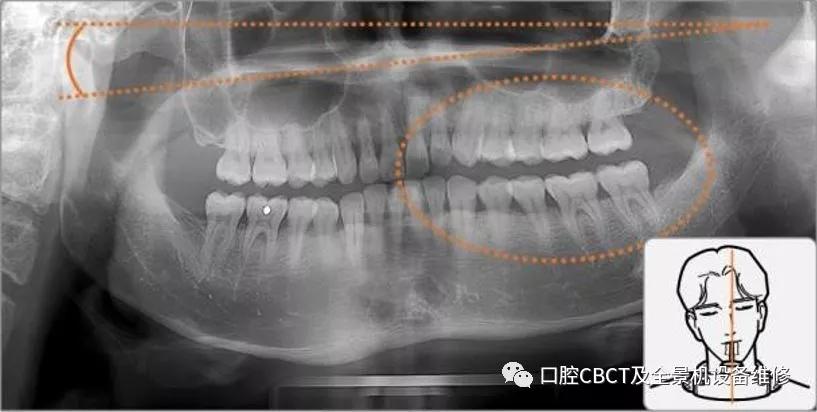

伯爵cbct影像篇③口腔全景片认知

图片尺寸1129x525

伯爵cbct影像篇 ③:口腔全景片认知

图片尺寸1246x795